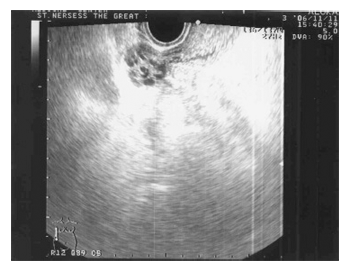

Второй тип эхограммы яичников выявлен у 23,4% (11) больных с АО. В максимальном эхографическом срезе яичника определялись 2-3 фолликула диаметром 0,5-0,6см с четким контуром и 1-2 фолликула диаметром до 1,2±0,1см. Эхогенность стромы повышена. Эхографически граница между корковым и мозговым веществом яичников прослеживалась неотчетливо. AFC очень низкий – 3-4. Темп роста фолликулов был неравномерный (в среднем 0,2см за 7 дней); временная организация атретических фолликулов была не детерминирована (рис.2). В процессе мониторинга наблюдалась эхографическая динамика структуры М-эхо от эхопозитивной линии толщиной 0,2см до двухконтурного эндометрия толщиной 0,4см, позволяющая предполагать пролиферативную трансформацию эндометрия в ответ на суммарную активность незрелых фолликулов. Среди больных с АО II тип эхограммы яичников наблюдался как у больных с опсоолигоменореей, так и с вторичной аменореей.

Рис. 2. II тип эхограммы яичников и ее схематическое изображение Разновеликие фолликулы с неравномерным темпом роста.